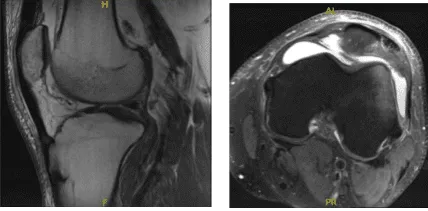

A result for MRI was presented and shown mildly displaced patellar fracture with accompanying longitudinal tear of the distal quadriceps tendon. Bone contusion of the lateral femoral condyle. Large left knee joint effusion. Minimal undersurface fraying along the course of the medial meniscal posterior horn.

MRI – 3T Left Knee Non Contrast